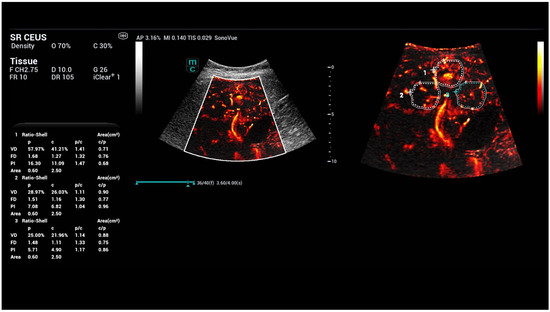

High-Resolution Contrast-Enhanced Ultrasound with SRCEUS for Assessing the Intrahepatic Microvasculature and Shunts in Patients with Hereditary Haemorrhagic Teleangiectasia (Osler’s Disease)

3. Results

| diameter: close to the capsule | 5133.7 ± 1456.6 | 1972.3 + 399.2 | 6.18989 × 10−13 |

| diameter: at the level of the portal vein | 2175.3 ± 417.5 | 2890.7 + 606.9 | 3.00779 × 10−11 |

| area: close to the capsule | 68.9 ± 8.8 | 8.9 + 1.99 | 1.4051 × 10−26 |

| area: at the level of the portal vein | 35.8 ± 7.73 | 16.8 + 3.66 | 8.29298 × 10−15 |